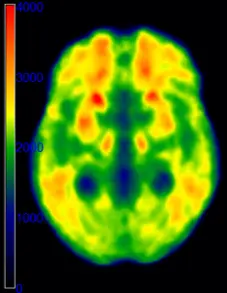

High iron load in the brain, deleterious to brain integrity and cognitive performance, has been observed in normal and pathological aging. We investigate the impact of brain iron on neural activity and cognitive performance in aging. Another aim is to uncover the genetic, physiological and lifestyle determinants of brain iron accumulation.

The project is funded by the Swedish Research Council, Alzheimerfonden and Karolinska Institutet (KI grant and KID funding).

PI: Grégoria Kalpouzos

We assess the role of brain iron and microbleeds in cognitive and physical function in a population-based study on aging (SNAC-K). One aspect of this project is the automated segmentation of iron-rich small nuclei using deep learning.

This project is funded by the Swedish Research Council.